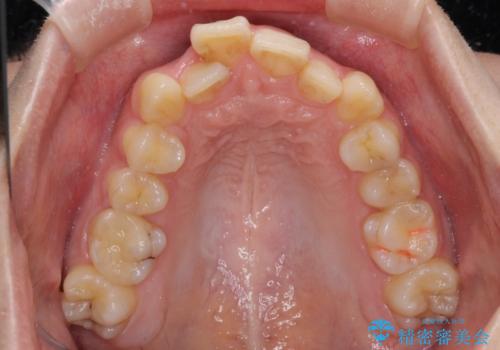

- 前歯のデコボコを気にして来院された患者様です。

上下の前歯にデコボコがあり、更にはディープバイトにより下顎前歯の大半が隠れている状態でした。

上顎左右第一小臼歯の2本を抜歯し、ワイヤー装置を使用して咬み合わせ高さを改善しながら、歯列を整えて行くこととしました。